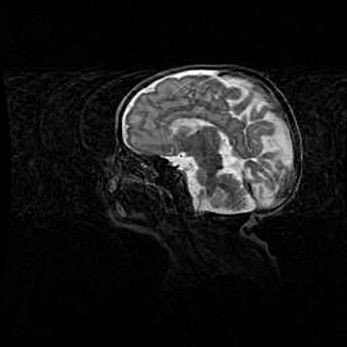

Множественные кисты обоих полушарий головного мозга, наибольшая из них в правой затылочной области. Ассиметричная атрофическая гидроцефалия.

Возраст: 7 месяцев

Вес: 5660 г

Пол: мужской

Окружность головы: 41,5 см

Срок гестации: 28-29 недель

Кисты головного мозга развиваются в результате многоочаговых некрозов вещества мозга и возникают вследствие перенесенной перинатальной инфекции, менингитов, энцефалитов, асфиксии, родовой травмы, расстройств мозгового кровообращения различного генеза. Образованию кист в веществе головного мозга плодов и новорожденных способствуют такие факторы, как высокое содержание в нем воды, недостаточная (или отсутствие) миелинизация и слабая астроглиальная реакция на повреждение.

Кисты могут сочетаться с гидроцефалией и другими поражениями головного мозга.